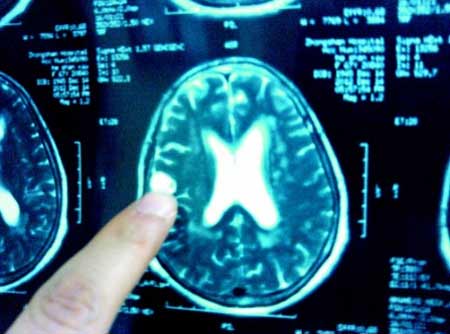

Bà Hà là một giáo viên nghỉ hưu ở Hồ Bắc, ngày 10/12 , bà đột ngột bị hoa mắt chóng mặt và nôn mửa nhiều lần. Ngày 14/12, đi khám thì bác sĩ phát hiện tắc mạch máu não và được chuyển lên bệnh viện Trung Sơn tỉnh Hồ Bắc (Trung Quốc). Sau khi trải qua hàng loạt kiểm tra hóa nghiệm, bác sỹ phát hiện trong não có 2 khối di động trong não và chứa đầy sán.

Ổ trùng được chụp từ trong não bệnh nhân

Theo bác sĩ Bành, Trưởng khoa nội thần kinh bệnh viện Trung Sơn, thông thường, sau khi người bệnh ăn phải thực phẩm có các nang sán, các nang này sẽ bám theo hệ thống tĩnh mạch và đường ruột và cuối cùng “định cư” ở não bộ và phát triển thành sán. Hoạt động của những con sán này sẽ phá hủy mô não, từ đó gây ra đau đầu, nôn mửa hoặc chứng động kinh.